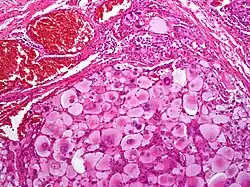

Tłuszczakomięsak wielopostaciowy (polimorficzny, pleomorficzny)

Jest to mięsak o dużym stopniu złośliwości. Zlokalizowany jest głównie w głębokich tkankach miękkich w obrębie kończyn, częściej w kończynie dolnej niż górnej. Rzadziej występuje w tułowiu, przestrzeni pozaotrzewnowej, śródpiersiu, skalpie, w okolicy jąder i oczodole. Stanowi poniżej 5% wszystkich typów tłuszczakomięsaków[18][16]. Makroskopowo często jest to twardy, wieloogniskowy, duży guz o średnicy nawet powyżej 10 cm o kolorze białym do żółtego. W wielu przypadkach występują strefy martwicy lub śluzowate obszary[19]. Mogą być guzami dobrze odgraniczonymi lub naciekającymi. Mikroskopowo jest zbudowany z różnej liczby polimorficznych lipoblastów w tle do wielopostaciowego mięsaka. Zwykle nowotwór składa się z wrzecionowatych komórek nowotworowych o wielu postaciach oraz pęczków wrzecionowatych i okrągłych komórek przemieszanych z wielojądrzastymi gigantycznymi komórkami (podobnymi do komórek niezróżnicowanego mięsaka pleomorficznego – UPS). Również może składać się z polimorficznych, wielowodniczkowych lipoblastów z dziwacznymi, hiperchromatycznymi, półokrągłymi jądrami. Często są widoczne wewnątrzkomórkowe lub zewnątrzkomórkowe eozynofilne kropelki, rzadko występuje naciek zapalny[19][20]. Choć ten typ tłuszczakomięsaka zawiera wielopostaciowe lipoblasty, to brak wysoko zróżnicowanych składników tłuszczakowatych odróżnia go od typu odróżnicowanego[9]. Klinicznie bardzo często występują przerzuty, które dotyczą aż 50% chorych. Początkowo lokalizują się w płucach[16].